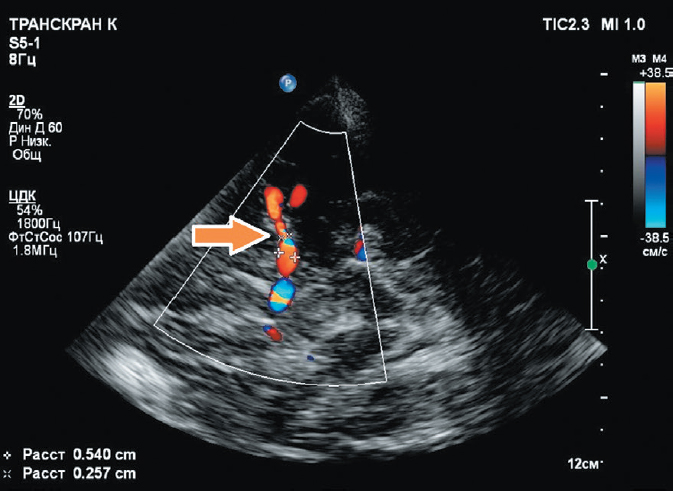

Clinical Case 1: a 63-year-old man with a mine-blast injury and shrapnel gunshot wounds to the head, neck, chest, abdomen, and extremities:

- Floating thrombus of the right common carotid artery (Figs. 3 and 4);

Fig. 3. Duplex ultrasonography of the cervical vessels. Foreign bodies (fragments and markers 1 and 2) adjacent to the posterior wall of the right common carotid artery. Floating intraluminal thrombus of the posterolateral wall of the middle third of the right common carotid artery (markers 3 and 4). Nonstenotic carotid atherosclerosis.